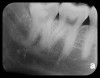

There are two specific types of DIDR sensor systems available to dentists in the marketplace: the hard-wired (HW) sensor and the photostimulable phosphor (PSP) sensor,1,2 also commonly known as phosphor "plates." A desirable feature common to both modalities is the ability to expose either bitewing (BW) or PA radiographic images. The BW radiograph (Figure 1) is usually considered more appropriate for caries detection, whereas the PA (Figure 2) is diagnostic for several different anatomic and pathologic issues.7

Fig 1. Left: Representative PSP BW radiograph with multiple restorative materials of varying radiographic densities. Tooth No. 31 demonstrates deep

caries on mesial aspect beneath the restorative. Radiolucency of carious lesion results from the low relative density of caries compared with healthy

tooth structure. Right: PSP BW radiograph optimized for view of multiple interproximal carious lesions.

Figure 1